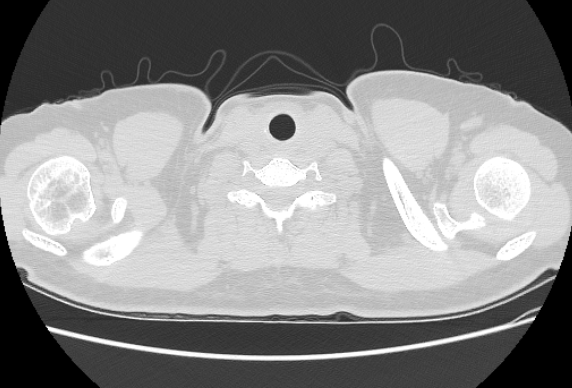

CTA MRI Brain

MRI Brain X-Ray

CT Abdomen MRI Spine

MRI Spine AI Case